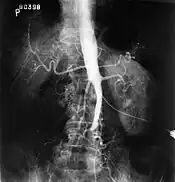

The physical examination usually shows weakened femoral pulses and a reduced ankle-brachial index. The diagnosis can be verified by color duplex scanning, which reveals either a peak systolic velocity ratio ≥2.5 at the site of stenosis and/or a monophasic waveform. MRA and multidetector CTA are often used to determine the extent and type of obstruction. Another technique is digital subtraction angiography which allows verification of the diagnosis and endovascular treatment in a single session.[2]

Angiography provides important information regarding the perfusion and patency of distal arteries (e.g. femoral artery). The presence of collateral arteries in the pelvic and groin area is important in maintaining crucial blood flow and lower limb viability. However, angiography should only be used if symptoms warrant surgical intervention.[2]